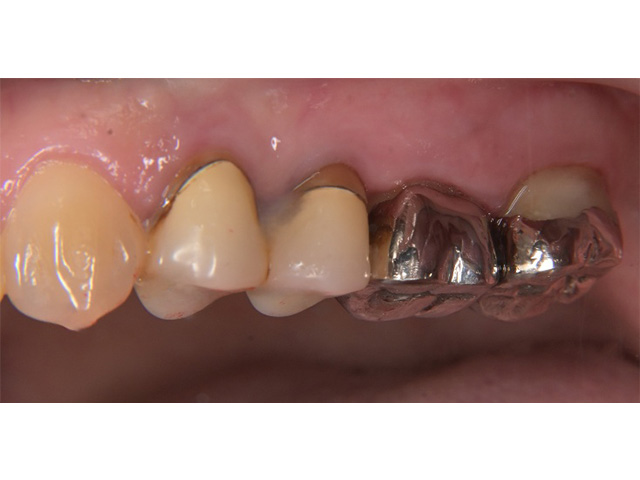

Before

After

| 主訴 | 右上の奥歯が咬むと痛む |

| 治療内容 | 右上第一大臼歯、第二大臼歯の精密根管治療 |

| 治療回数・期間 | 3回(3週間) |

| 費用 | 保険適応 |

| リスク・副作用 | 根管治療は術前の精密な診査診断および無菌環境下での治療によって成功率は高まってきましたが治療の成否を決める多くの要素があるため、根管治療がなされた後も再治療や外科処置、抜歯となる可能性が少なからずあります。また治療中には器具の破折や穿孔、修復物の損傷、歯の破折、術中・術後の痛みや腫れが生じることが稀にあります。根尖病変(再感染)を防ぐには適合の良好な補綴物を作製することや定期的なかみ合わせのチェックが必要です。 |